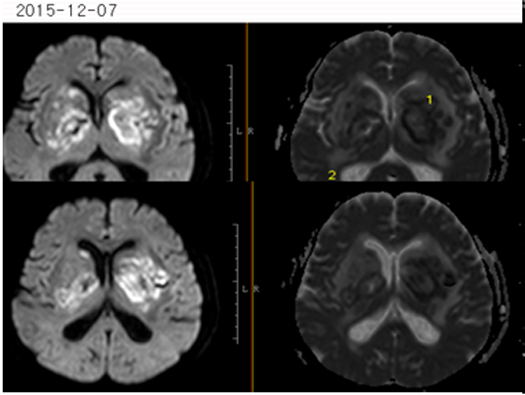

影像资料:

2015-11-27MR:双侧基底节区及双侧大脑脚示较对称片状异常信号, T1WI呈不匀低信号影,T2WI呈不匀高信号影,FLAIR序列呈不匀高信号,累及视交叉、视束及部分丘脑。2015-12-04复查:双侧基底节区及双侧大脑脚病灶范围较前稍增大。2015-12-07增强后病变呈多发环形薄壁或片状强化,DWI呈不均匀高信号。右侧基底节区病灶感兴趣区,可见Cho峰、NAA峰及Cr峰,Cho峰未见明显升高,Cho/Cr比值约为0.34,NAA/Cr比值约为0.56,Cho/NAA比值约0.61。综合平扫、增强、DWI、MRS所见,可排除肿瘤性病变,支持感染性病变(真菌或病毒感染可能性大)。